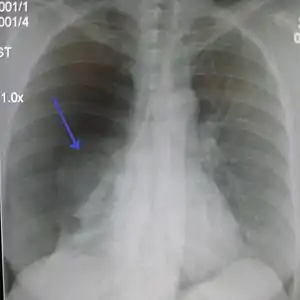

Chest X-ray

A plain chest radiograph, ideally with the X-ray beams being projected from the back (posteroanterior, or "PA"), and during maximal inspiration (holding one's breath), is the most appropriate first investigation.[25] It is not believed that routinely taking images during expiration would confer any benefit.[26] Still, they may be useful in the detection of a pneumothorax when clinical suspicion is high but yet an inspiratory radiograph appears normal.[27] Also, if the PA X-ray does not show a pneumothorax but there is a strong suspicion of one, lateral X-rays (with beams projecting from the side) may be performed, but this is not routine practice.[14][18]

Anteroposterior expired X-ray at the same time, more clearly showing the pneumothorax in this case

The size of the pneumothorax (i.e. the volume of air in the pleural space) can be determined with a reasonable degree of accuracy by measuring the distance between the chest wall and the lung. This is relevant to treatment, as smaller pneumothoraces may be managed differently. An air rim of 2 cm means that the pneumothorax occupies about 50% of the hemithorax.[14] British professional guidelines have traditionally stated that the measurement should be performed at the level of the hilum (where blood vessels and airways enter the lung) with 2 cm as the cutoff,[14] while American guidelines state that the measurement should be done at the apex (top) of the lung with 3 cm differentiating between a "small" and a "large" pneumothorax.[28] The latter method may overestimate the size of a pneumothorax if it is located mainly at the apex, which is a common occurrence.[14] The various methods correlate poorly but are the best easily available ways of estimating pneumothorax size.[14][18] CT scanning (see below) can provide a more accurate determination of the size of the pneumothorax, but its routine use in this setting is not recommended.[28]